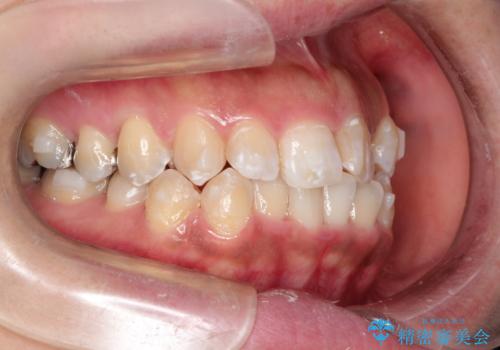

奥歯の噛み合わせは綺麗に噛んでいたため、前歯の叢生(でこぼこ)に集中して治療するように計画しました。

奥歯の噛み合わせは整っていたため、前歯の並びを美しく修正することに専念できました。